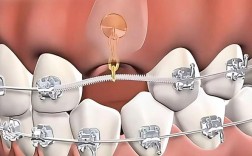

| 隐形矫治技术 | 总结附件设计“10项原则”,研发动态控根技术 | 提高隐形矫治对复杂错颌的矫治能力,拓展适应症范围 |